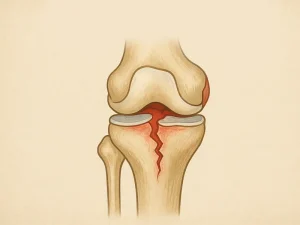

پارگی منیسک زانو یکی از شایعترین آسیبهای زانو است که